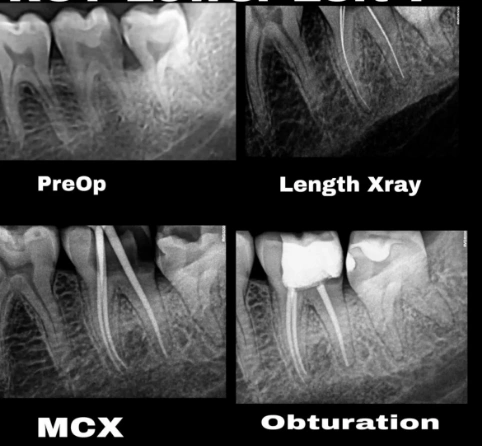

Advanced Root Canal Treatment with Precision Endodontic Care

Root canal treatment is a specialised dental procedure designed to remove infection from inside the tooth and protect it from further damage. At Om Dental, we approach root canal treatment in Koparkhairane with a clear goal, eliminate pain, preserve your natural tooth, and restore comfortable chewing.

Microscope-Assisted Root Canal

It involves enhanced precision while using dental microscopes for complex canals and higher treatment success rates.